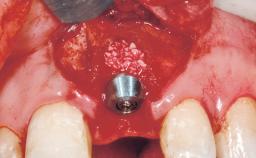

A 36-year-old female patient was referred for the replacement of the upper left central incisor (tooth 21), which had fractured. Although the tooth had been asymptomatic for many years, the crown began to loosen, at which time she presented to her dentist for an assessment. Teeth 21 and 22 had both been endodontically treated many years previously. She was a healthy individual and a non-smoker.

| Bone Augmentation | Horizontal|Staged |

| Bone Volume | Deficient horizontally, requiring prior grafting |